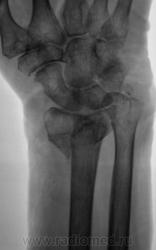

Травма. Пациентка направлена врачом хирургом на рентгенографию лучезапястного сустава.

На фоне умеренных артрозных изменений в л/з и мелких суставах кисти оскольчатый в/суставной разгибательнуй перелом лучевой кости в т.м. с резко выраженным смещением под углом (около 120 гр), открытым дорзально. Перелом шиловидного отростка локтевой кости. Плохо вижу контур крючковатой кости по ульнарной поверхности.

Пациент направлен на рентгенографию лучезапястного сустава.

Вколоченный (или сколоченный) перелом лучевой кости с удовл. стоянием к/фрагментов неясной давности. в дист. отделах костей предплечья и, по-моему, костях запястья умеренный остеопороз. Очаг дестукции в головке 5-й пястной ? (вижу нечетко, погрешность передачи изображения?)

Заслуживают также внимание 4 и 5 пястные кости, особенно 4 пястная кость.

4 пястная грацильна, но структуру ее , к сожалению, рассмотреть не удается.Кроме остеопороза в ее проксим. конце и истончения кортикального слоя ничего не вижу.